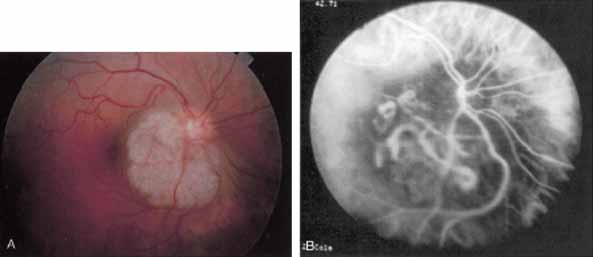

Idiopathic polypoidal choroidal vasculopathy, also known as posterior uveal bleeding syndrome, typically affects darkly pigmented persons who exhibit acute exudative manifestations in the posterior pole, including subretinal hemorrhage and, occasionally, CNV.76,77 ICG angiography facilitates a more definitive diagnosis than fluorescein angiography because it achieves a sharper image of the primary lesion,51,77,78 dilated choroidal vessels terminating in polypoidal or aneurysmal excrescences at the level of the choroid (Fig. 23). These vascular changes account for the secondary exudative and hemorrhagic detachments of the retinal pigment epithelium and neurosensory retina that are characteristic of this disorder. Furthermore, ICG angiography may provide a better means of differentiating the relatively benign aneurysm-like changes at the level of the larger choroidal vessels from CNV, a more devastating secondary manifestation of this chronic disease.79

Fig. 23 A. Clinical photograph of a patient with idiopathic polypoidal choroidal vasculopathy demonstrating the branching lesion at the level of the choroid. There is a more nodular elevation in the inferior macula. A hemorrhagic detachment of the retina is noted temporally in a curvilinear fashion. B. “Green-free” photograph that more vividly demonstrates the branching vascular pattern of this condition. C. High-magnification image of an early-phase indocyanine green (ICG) study reveals filling of the vascular channels at the level of the choroid leading to the polypoidal lesions. Note that the inferior, more elevated lesion, which is nodular on clinical examination, consists of an internal network of branching vessels. D. Late-phase ICG study demonstrates ring-like staining of the small polypoidal lesions. The larger lesion shows intense but nonhomogeneous staining.